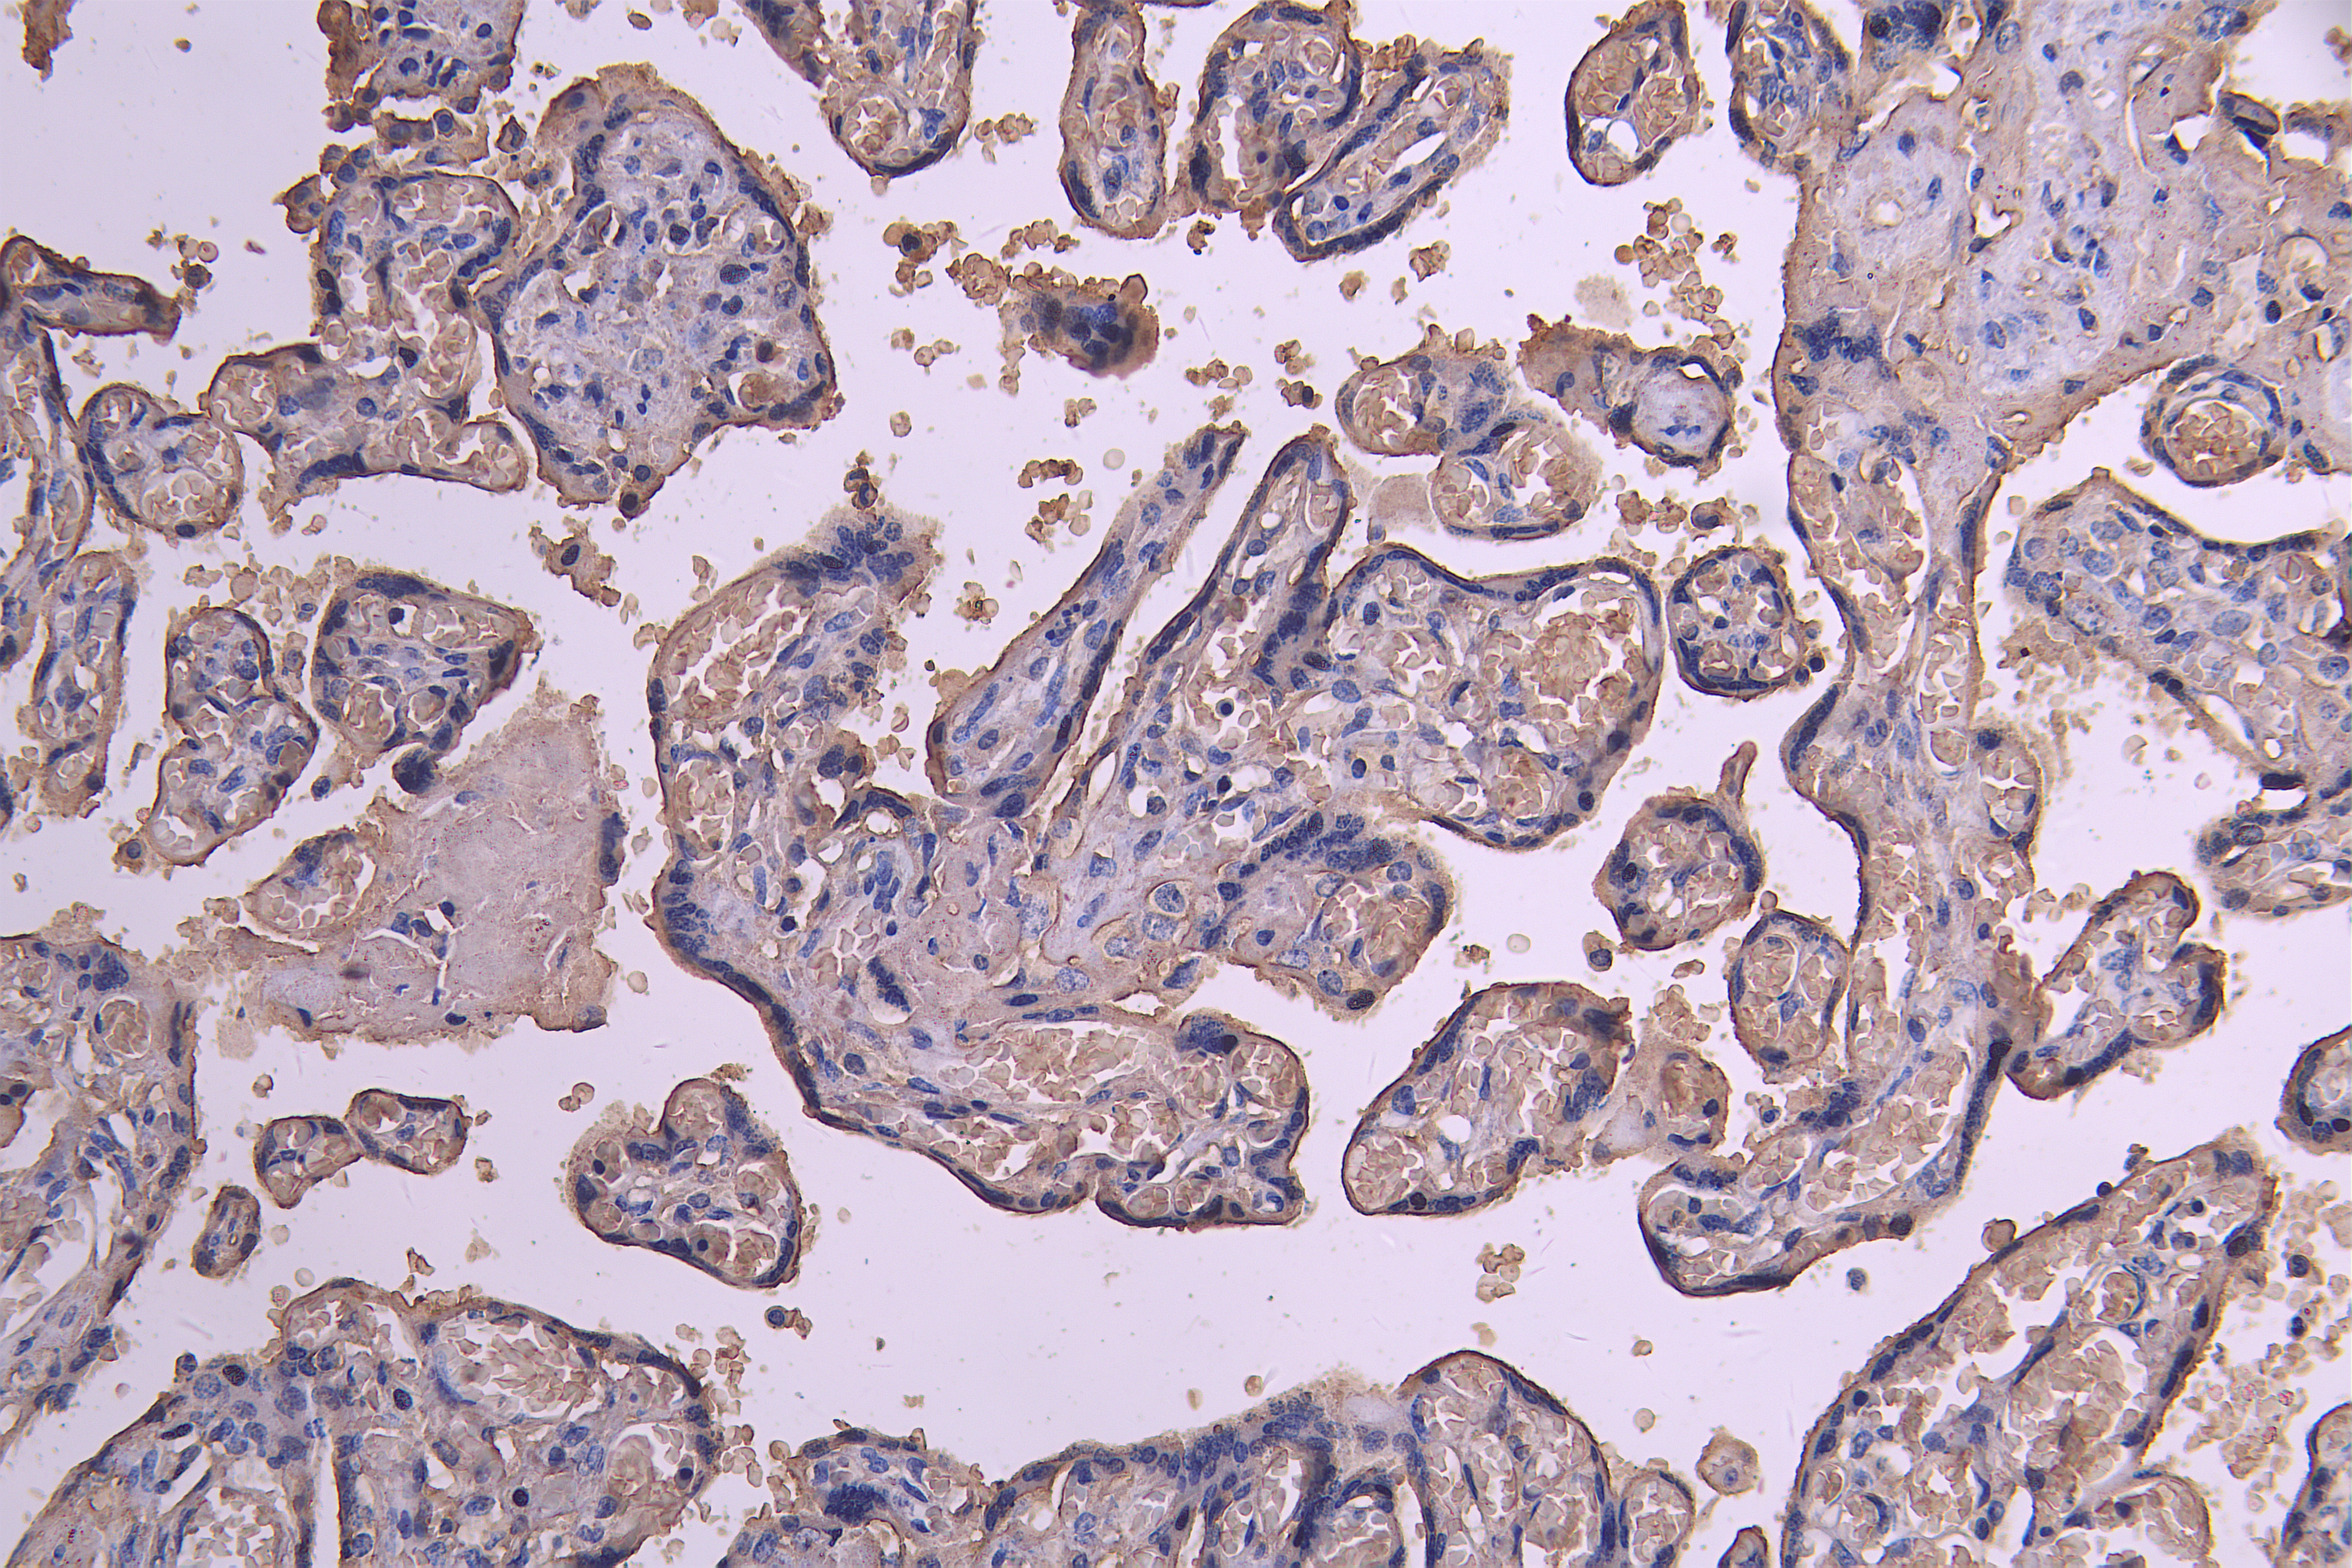

IHC image of CSB-RA623829MA1HU diluted at 1:200 and staining in paraffin-embedded human placenta tissue performed on a Leica BondTM system. After dewaxing and hydration, antigen retrieval was mediated by high pressure in a citrate buffer (pH 6.0). Section was blocked with 10% normal goat serum 30min at RT. Then primary antibody (1% BSA) was incubated at 4°C overnight. The primary is detected by a Goat anti-human polymer IgG labeled by HRP and visualized using 0.05% DAB.